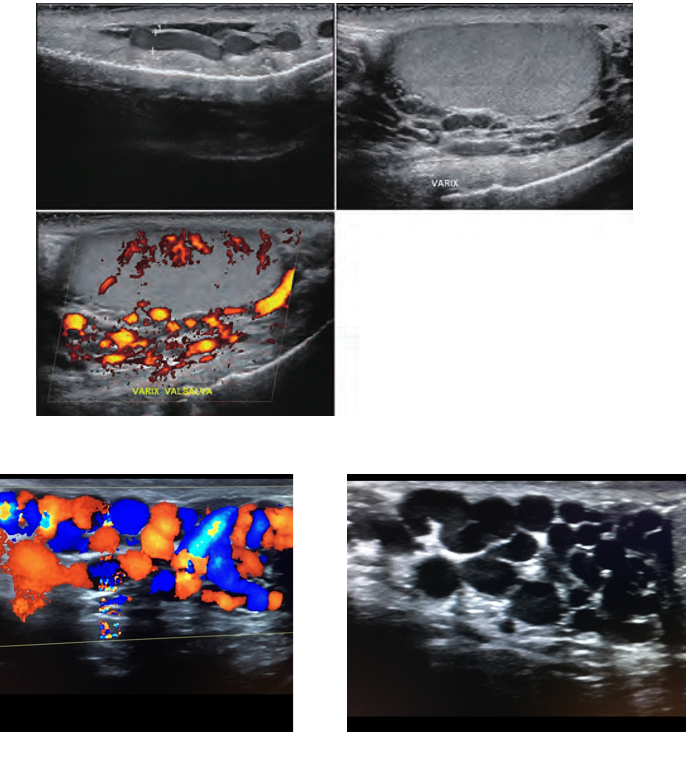

Varicocele

what does the image show

torsion

testicular tumour